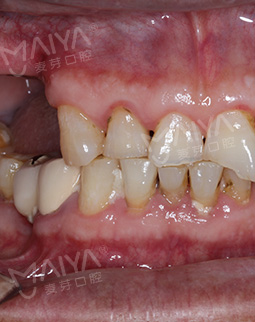

2017年4月7日 定制MAC数字化精确种植方案,牙骨重新长出来

由于缺牙时间过长,我的上颌骨量严重不足,种植牙条件也是非常艰巨,必须通过植骨手术来解决这一问题,并且上颌有动脉血管,手术时上颌开口误差要确保在3mm之内,如果手术过程中不小心割破血管,后果将不堪设想。考虑到这个情况,麦芽硕博智库团给我定制了MAC数字化精确种植方案。通过GBR骨引导再生使骨量重新长出来,提高植体稳定性。上颌窦的底壁提升到原先位置从而获得足够的种植空间,避免植体周围炎,半年之后进行种植手术。

来到麦芽口腔后有专门的种植团队接待了我,经过拍片检查,再到医生给我看牙。了解了我的牙齿情况后,医生告诉我,符合做种植牙的条件。听到这个消息,真的十分高兴,“奔波了一个多月,本来没有指望能种上牙了,没想到最后在麦芽口腔看到了希望,别提有多高兴了!”